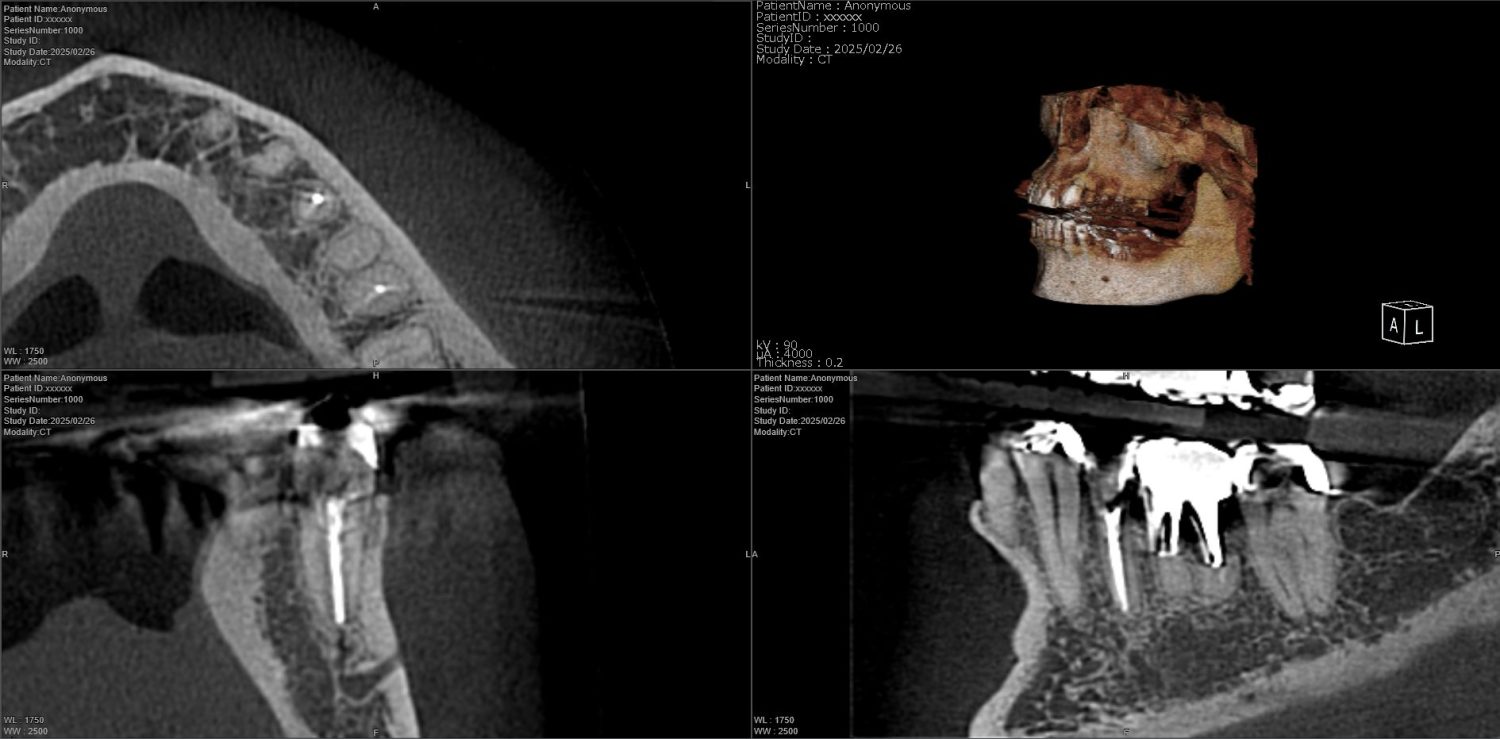

| 主訴 | 過去の治療にて根管充填後、噛むと違和感・痛みが出てきた。一度詰めた薬を撤去してもらったが症状が変わらなかったため来院。 |

| 治療内容 | ラバーダム防湿を行い、マイクロスコープにて根尖部の溢出ガッタパーチャの除去を行いました。 |

CT撮影により根尖部にガッタパーチャの溢出を確認。

拡大視野下にて残存ガッタパーチャを確認しながら過拡大に注意しながら除去。

その後根管充填を行った症例です。ガッタパーチャ除去したことで症状が改善されました。